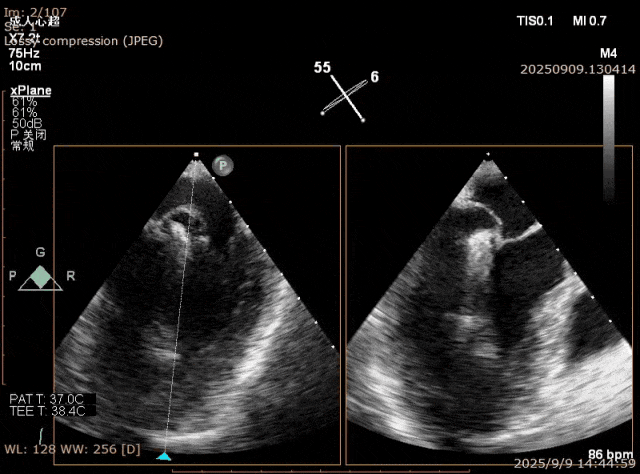

在一些退行性二尖瓣(DMR)病例中,由于二尖瓣连枷瓣叶甩动厉害,两个瓣叶之间的连枷间隙过大,难以充分夹合瓣叶:二尖瓣瓣叶甩动形成了拱形结构,经股静脉夹子摆动式的设计只能捕获到拱形的下降支,或在关闭时瓣叶仍在甩动导致瓣叶滑脱。一些技巧可以帮忙克服这一难点,包括快速起搏、腺苷或者拉链技术,但这些操作都偏复杂。一个简单方法就是将下夹臂反转到210度以上,让瓣叶充分插入到上下夹臂之间夹角内,然后较快速关闭夹子(图5-7)。该方法可以配合分别捕获技术提高夹合的成功率。无论刚性夹和弹性夹,该技术都可以应用。

图5. Barlow样改变,A3,P2, P3脱垂,后叶甩动厉害

图6. XTR 一枚夹合 2区,后叶难以夹多

图7. 倒挂金钩,夹合更多瓣叶